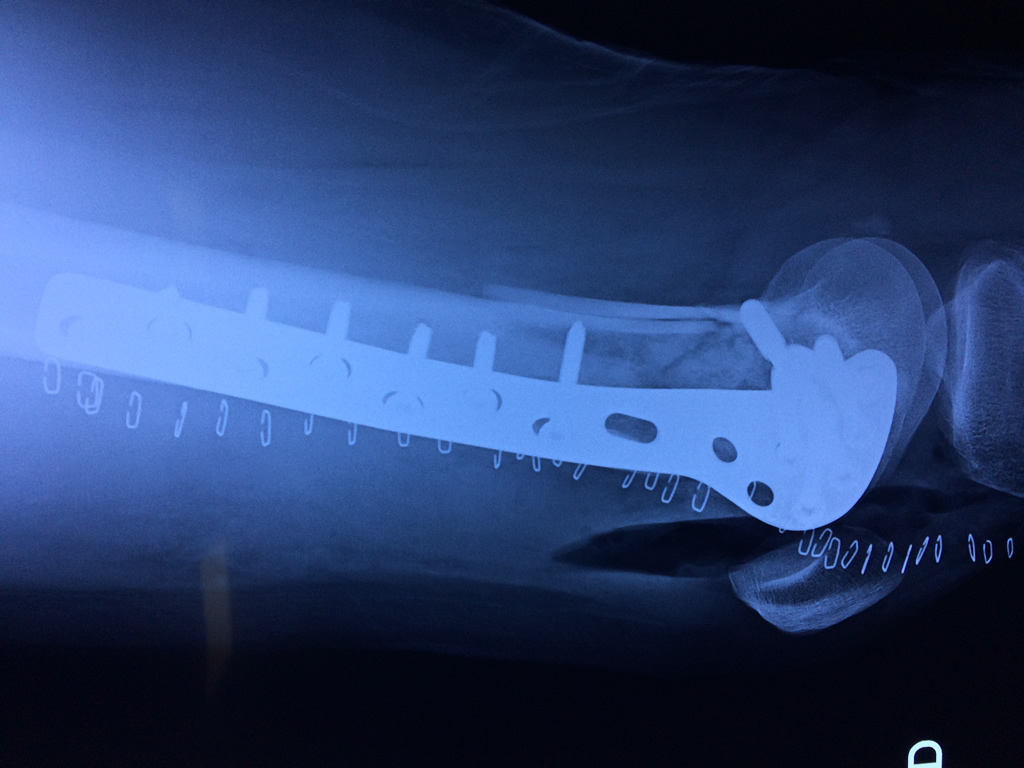

Cirugías de Peroné y Tibia